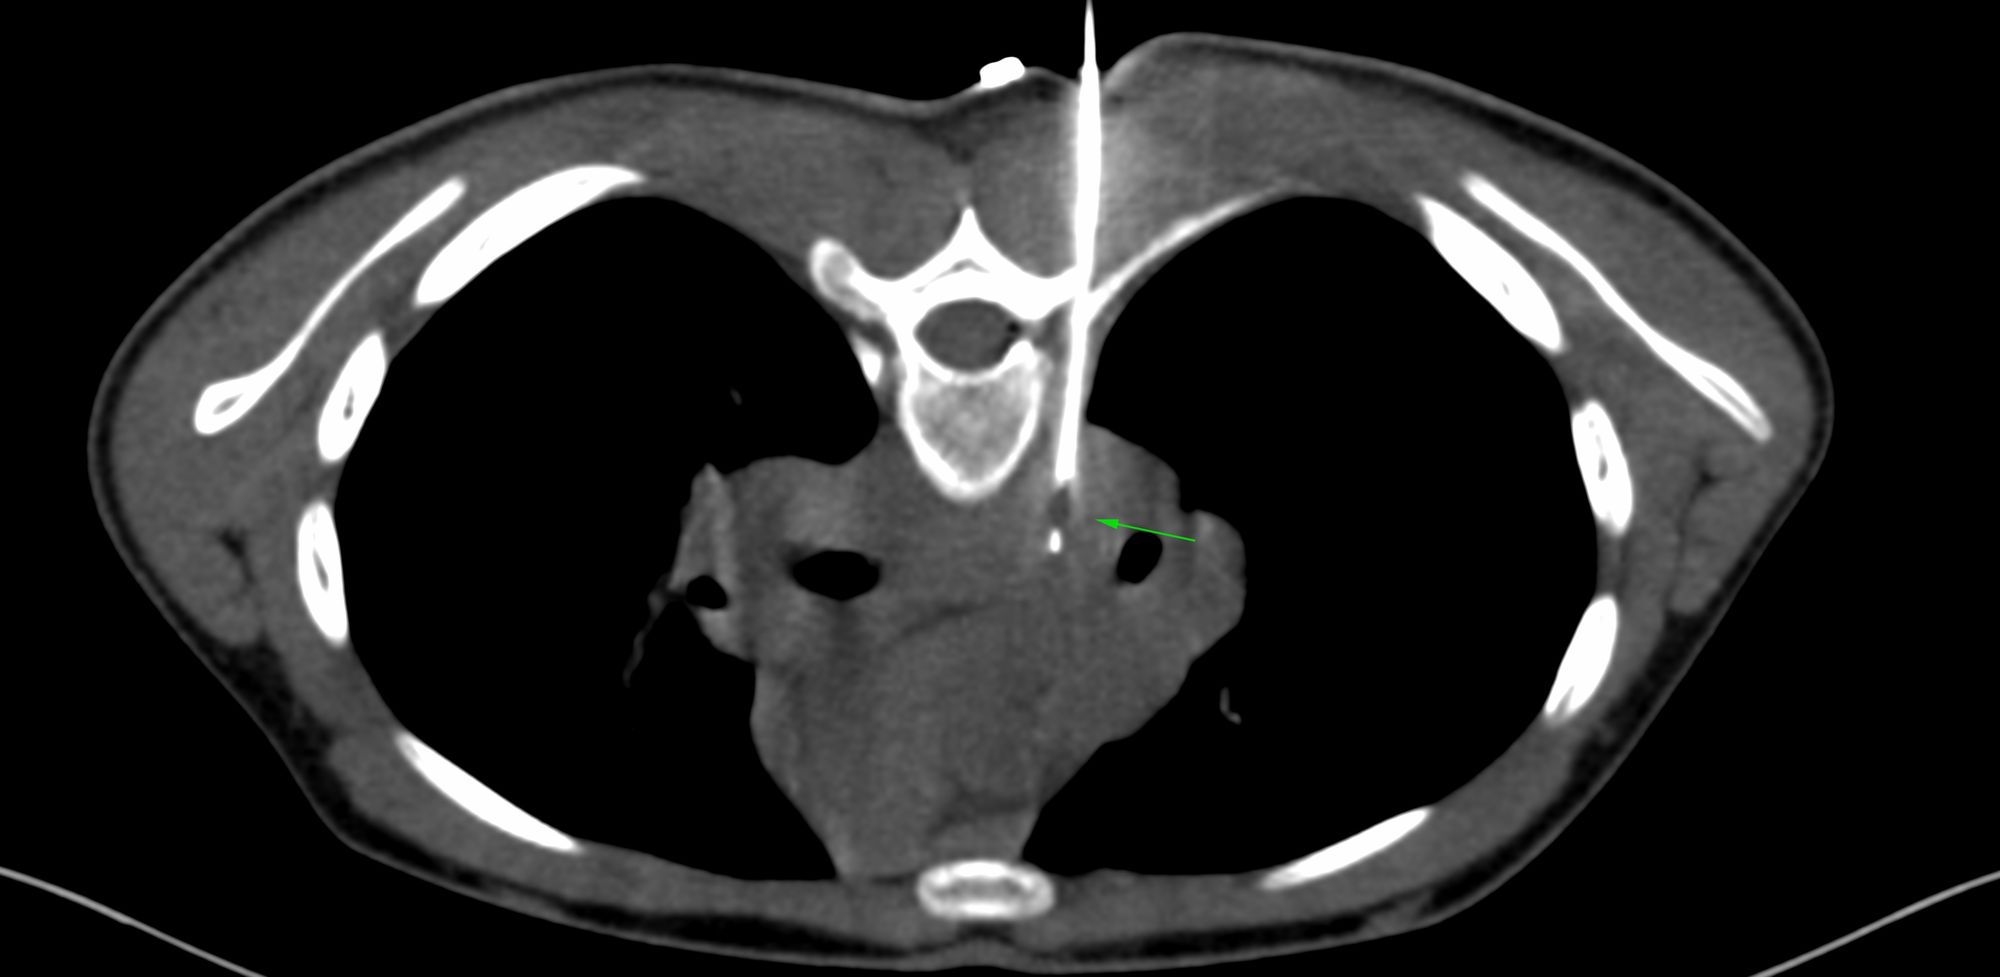

Case 69: Whose Responsibility is It After a Negative Biopsy to Push for a Repeat Biopsy?

Bhavin Jankharia - 03 December 2021